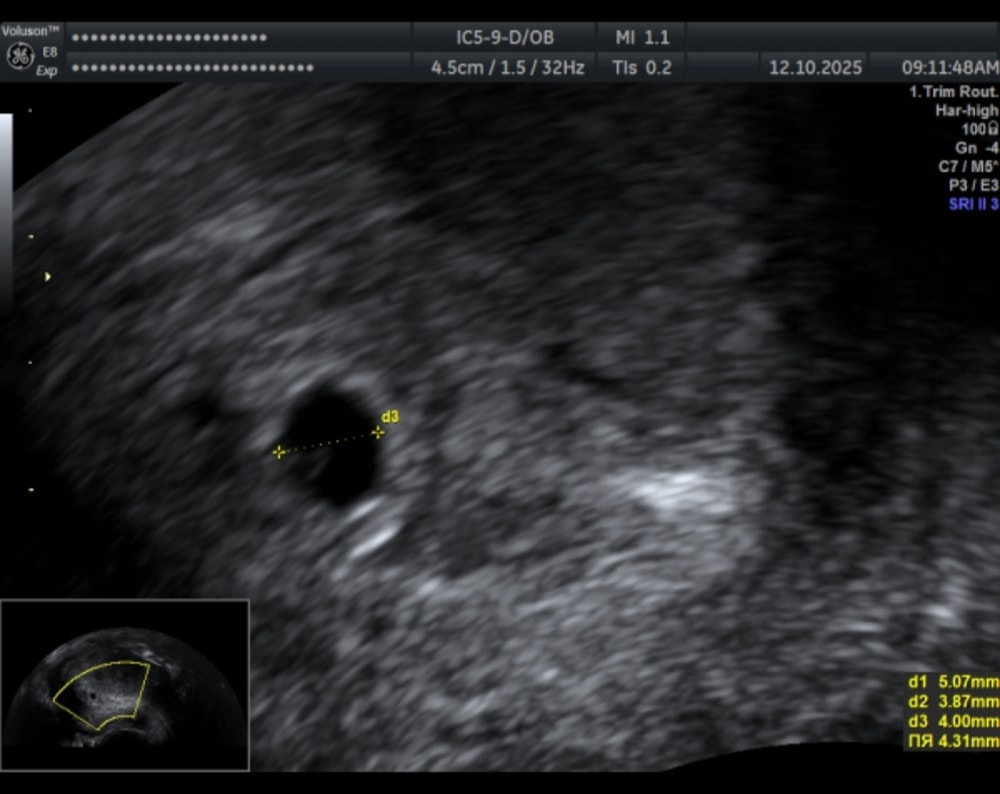

5,6 недель. Узи❣️

Беременность- 1 триместр ( только до 10 недель)Сегодня пошла на первое узи😊

Сразу нашли мою крошку. Неожиданно для меня нашли и пя, и жм, и эмбрион. Я думала, с учётом того, что хгч 10 был 910,что там будет только ПЯ.

Пока крошка совсем мал🥹 КТР 1,2.